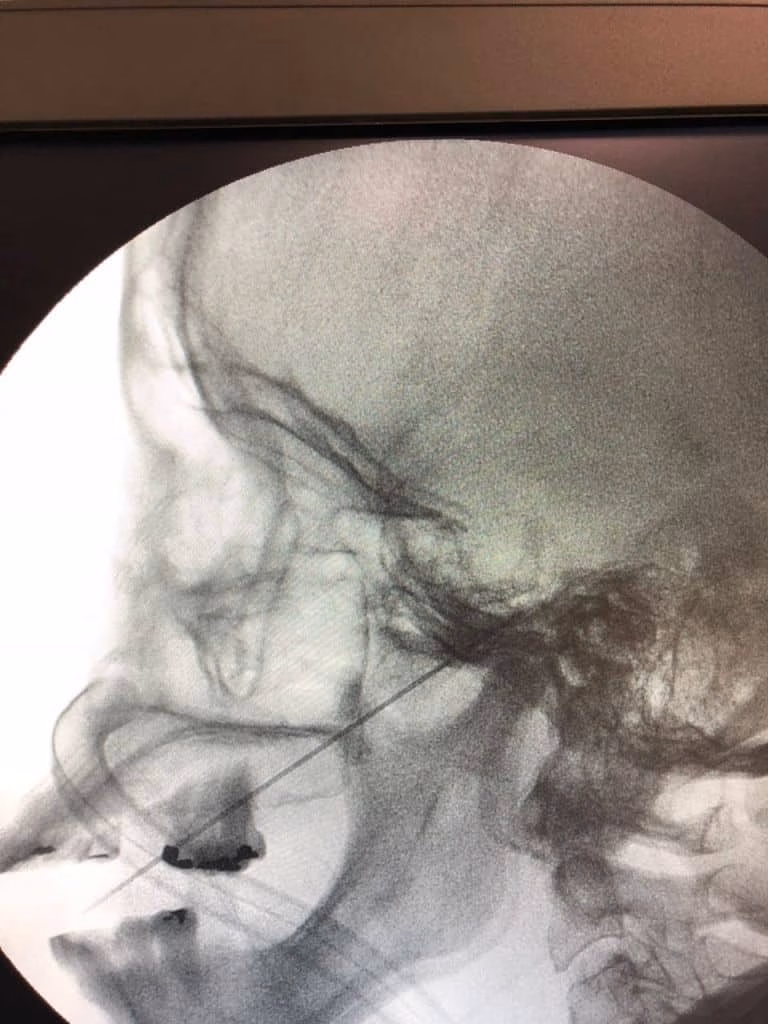

A rizotomia, como demonstrada na imagem, é realizada através de uma punção com agulha na face guiada por raio X. Em seguida é realizada lesão do nervo trigêmeo através de calor, compressão ou química. É um procedimento seguro e com uma taxa de melhora imediata da dor em torno de 90%.